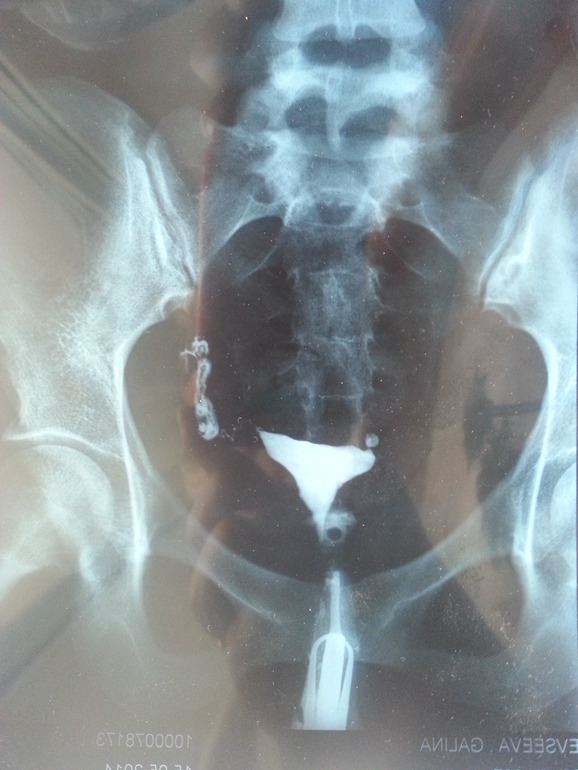

результаты ГСГ....минутная слабость....

результат: единственная труба частично проходима....перетурбарные спайки, по результатам узи за 2 месяца овулька с правой стороны где трубы нет....

как смогла сфотала снимок....

Можно в больнице поднять протокол операции.там пошагово описано что делали и в каком состоянии 2труба.гсг штука малоинформативная, но на вашем снимке труба проходима-контраст вилился в бр.полость. но механическая проходимость єто еще не все